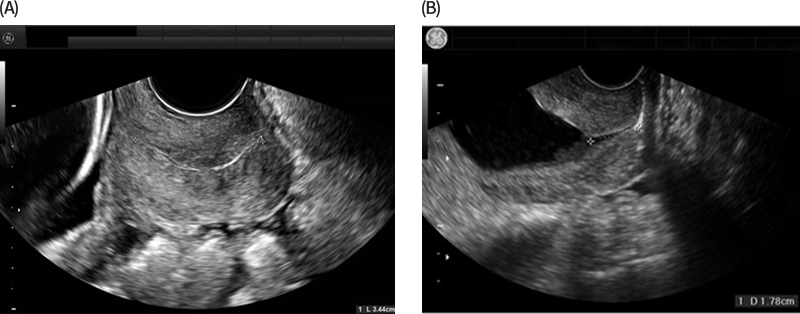

그림 1. Normal cervical length(A) and short cervix(B) as measured by transvaginal ultrasound (출처: GABBE’s Obstetrics 8th edition)

Short cervix의 정의는 다음과 같다: (1) 임신 24주 이전에 발견된 transvaginal ultrasound(TVU) cervical length(CL) <25mm 및/또는 자궁경부 변화, (2) 임신 37주 미만(일부에서는 34주 미만)의 이전 자발적인 조산(sPTB) 병력의 존재. TVU screening은 조산 예측을 위한 CL 평가의 gold standard이다. CL은 transabdominal or translabial ultrasound로도 측정할 수 있지만 TVU가 여러 면에서 우수하다. SMFM[1], ACOG[2] 등 CL screening을 설명하는 모든 주요 지침에서는 TVU를 명확하게 권장한다. TVU CL screening은 환자가 방광을 비운 후에 수행된다. Internal os에서 external os까지의 거리를 측정하려면 caliper를 올바르게 배치하는 것이 중요하다(그림 1). 일반적으로 CL을 3회 측정한 후 mild fundal pressure 또는 Valsalva를 약 15초 동안 적용하여 funneling and/or cervical shortening을 관찰하고 일반적으로 다시 3회 더 측정한다[3].